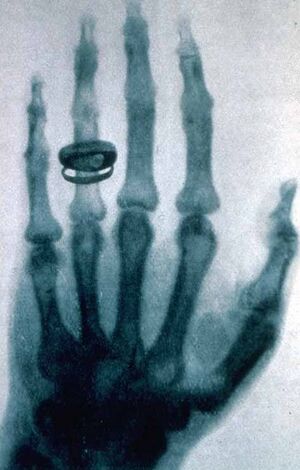

His hand was one of the first to be x-rayed, by his friend Wilhelm Röntgen.[3]

- ^ "RÖNTGEN, Wilhelm Conrad (1845–1923). Ueber eine neue Art von Strahlen (Vorläufige Mittheilung). – Eine neue Art von Strahlen. II. Mittheilung. Offprints from: Sitzungsberichte der Würzburger Physik.-medic. Gesellschaft, 1895 [no. 9], and 1896, [nos. 1–2]. Würzburg: Verlag und Druck der Stahel'schen k. Hof.-und Universitäts- Buch- und Kunsthandlung, 1895–1896". www.christies.com. Retrieved 3 أبريل 2019.